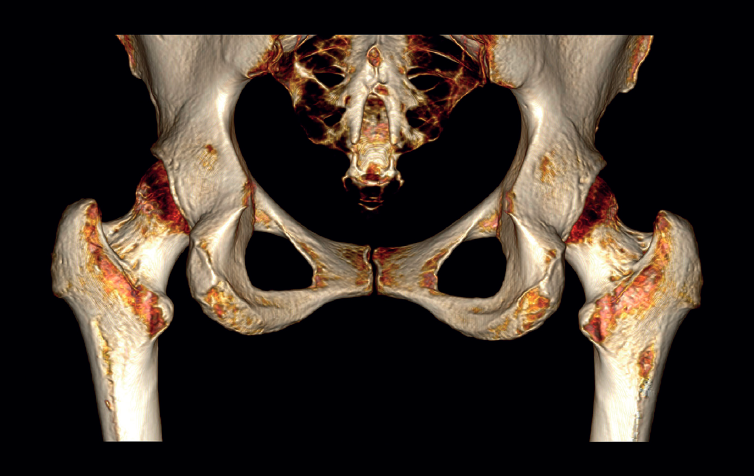

The physical examination revealed a limp-free gait and complete joint balance, with no positive signs of femoroacetabular impingement or inguinal pain. Muscle strength was preserved and similar to that of the contralateral side. She experienced intense pain on palpation of the insertion of the gluteus maximus, referred proximally to the ipsilateral buttock. The pain was reproduced on extension against resistance, and prevented sitting for long periods. Plain radiographic and computed tomography (CT) images revealed calcific tendinosis affecting the aponeurotic prolongation of the gluteus maximus in proximity to its insertion in the upper region of the linea aspera of the femur  (Figures 1 and 2) Magnetic resonance imaging (MRI) of the hip showed a labral tear, that proved asymptomatic in the physical examination. In view of the clinical picture of radicular pain, an MRI scan of the lumbar spine and subgluteal space was also performed, ruling out radicular involvement or sciatic neuritis. Her previous treatment over the three years of evolution of the disorder included oral nonsteroidal anti-inflammatory drugs, a specific physiotherapy programme and several ultrasound-guided corticosteroid injections with positive results - though a last session showed no response. Due to the severity and chronicity of the symptoms and their resistance to conservative treatment, surgery was decided to clean and remove the intratendon calcification endoscopically.

reacae.31181.fs2402007en-figure2.png